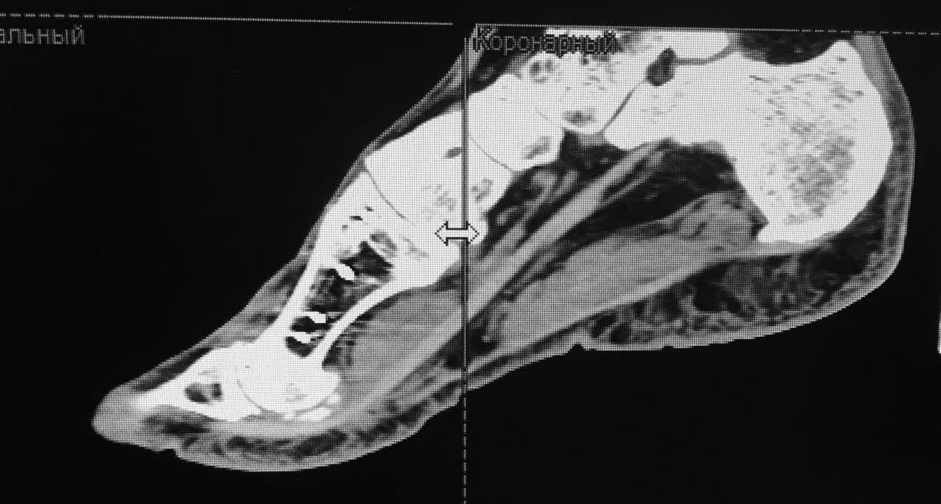

женщина средних лет, оперирована около года назад

заранее извиняюсь за скудность информации (консультация заочная). Насколько я понял, беспокоит метатарсалгия. Достаточно будет укоротить II-IV? Что-то другое? на что обратить внимание?

Судя по снимкам - болезнь Фрайберга по II лучу. Открытая моделирующая остеотомия головки II плюсневой и основания проксимальной фаланги II пальца, Weil с поднятие головки, III-IV лучи малоинвазивно.

Неутолимое желание поставить больше железок. 6 или 7 винтов и 2 пластины на одну плюсневую. Первичных снимков нет, но можно предположить, что 2 остеотомии привели к значительному укорочению М1. В результате - переходная метатарзалгия. Была или нет до операции деформация центральных пальцев тоже не знаем. Сейчас видны молоткообразная деформация второго пальца с преобладанием его длины над первым, перекрест второго и третьего пальцев. Если выпрямить второй - станет еще длиннее. А выпрямить может помешать отклоненный кнутри третий палец - второму некуда улечься. Поэтому нужно думать об остеотомии 2-4 плюсневых для устранения метатарзалгии (фиксированный или нефиксированный Вейль, DMMO - чем владеете), коррекции молоткообразной деформации второго (с его укорочением) и варусной деформации третьего пальца (возможно и четвертого, если будет мешать выпрямить третий). На болезнь Фрайберга не очень похоже. Скорее это подвывих пальца на некачественных снимках имитирует. В любом случае - моделирующая резекция - калечащая сустав операция. Декомпрессии за счет укорочения будет достаточно. Если есть возможность оперировать чрескожно - самый простой и беспроигрышный вариант.

Подвывих по 2-му лучу - большой. Может дополнительно подумать об удлинении разгибателей.